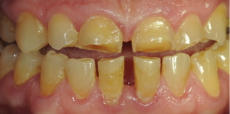

ДО

Пациент обратился с жалобой на истирание передней и боковой групп зубов, отсутствие жевательных зубов, затрудненное пережевывание пищи, ухудшение дикции, появление морщин в уголках рта.